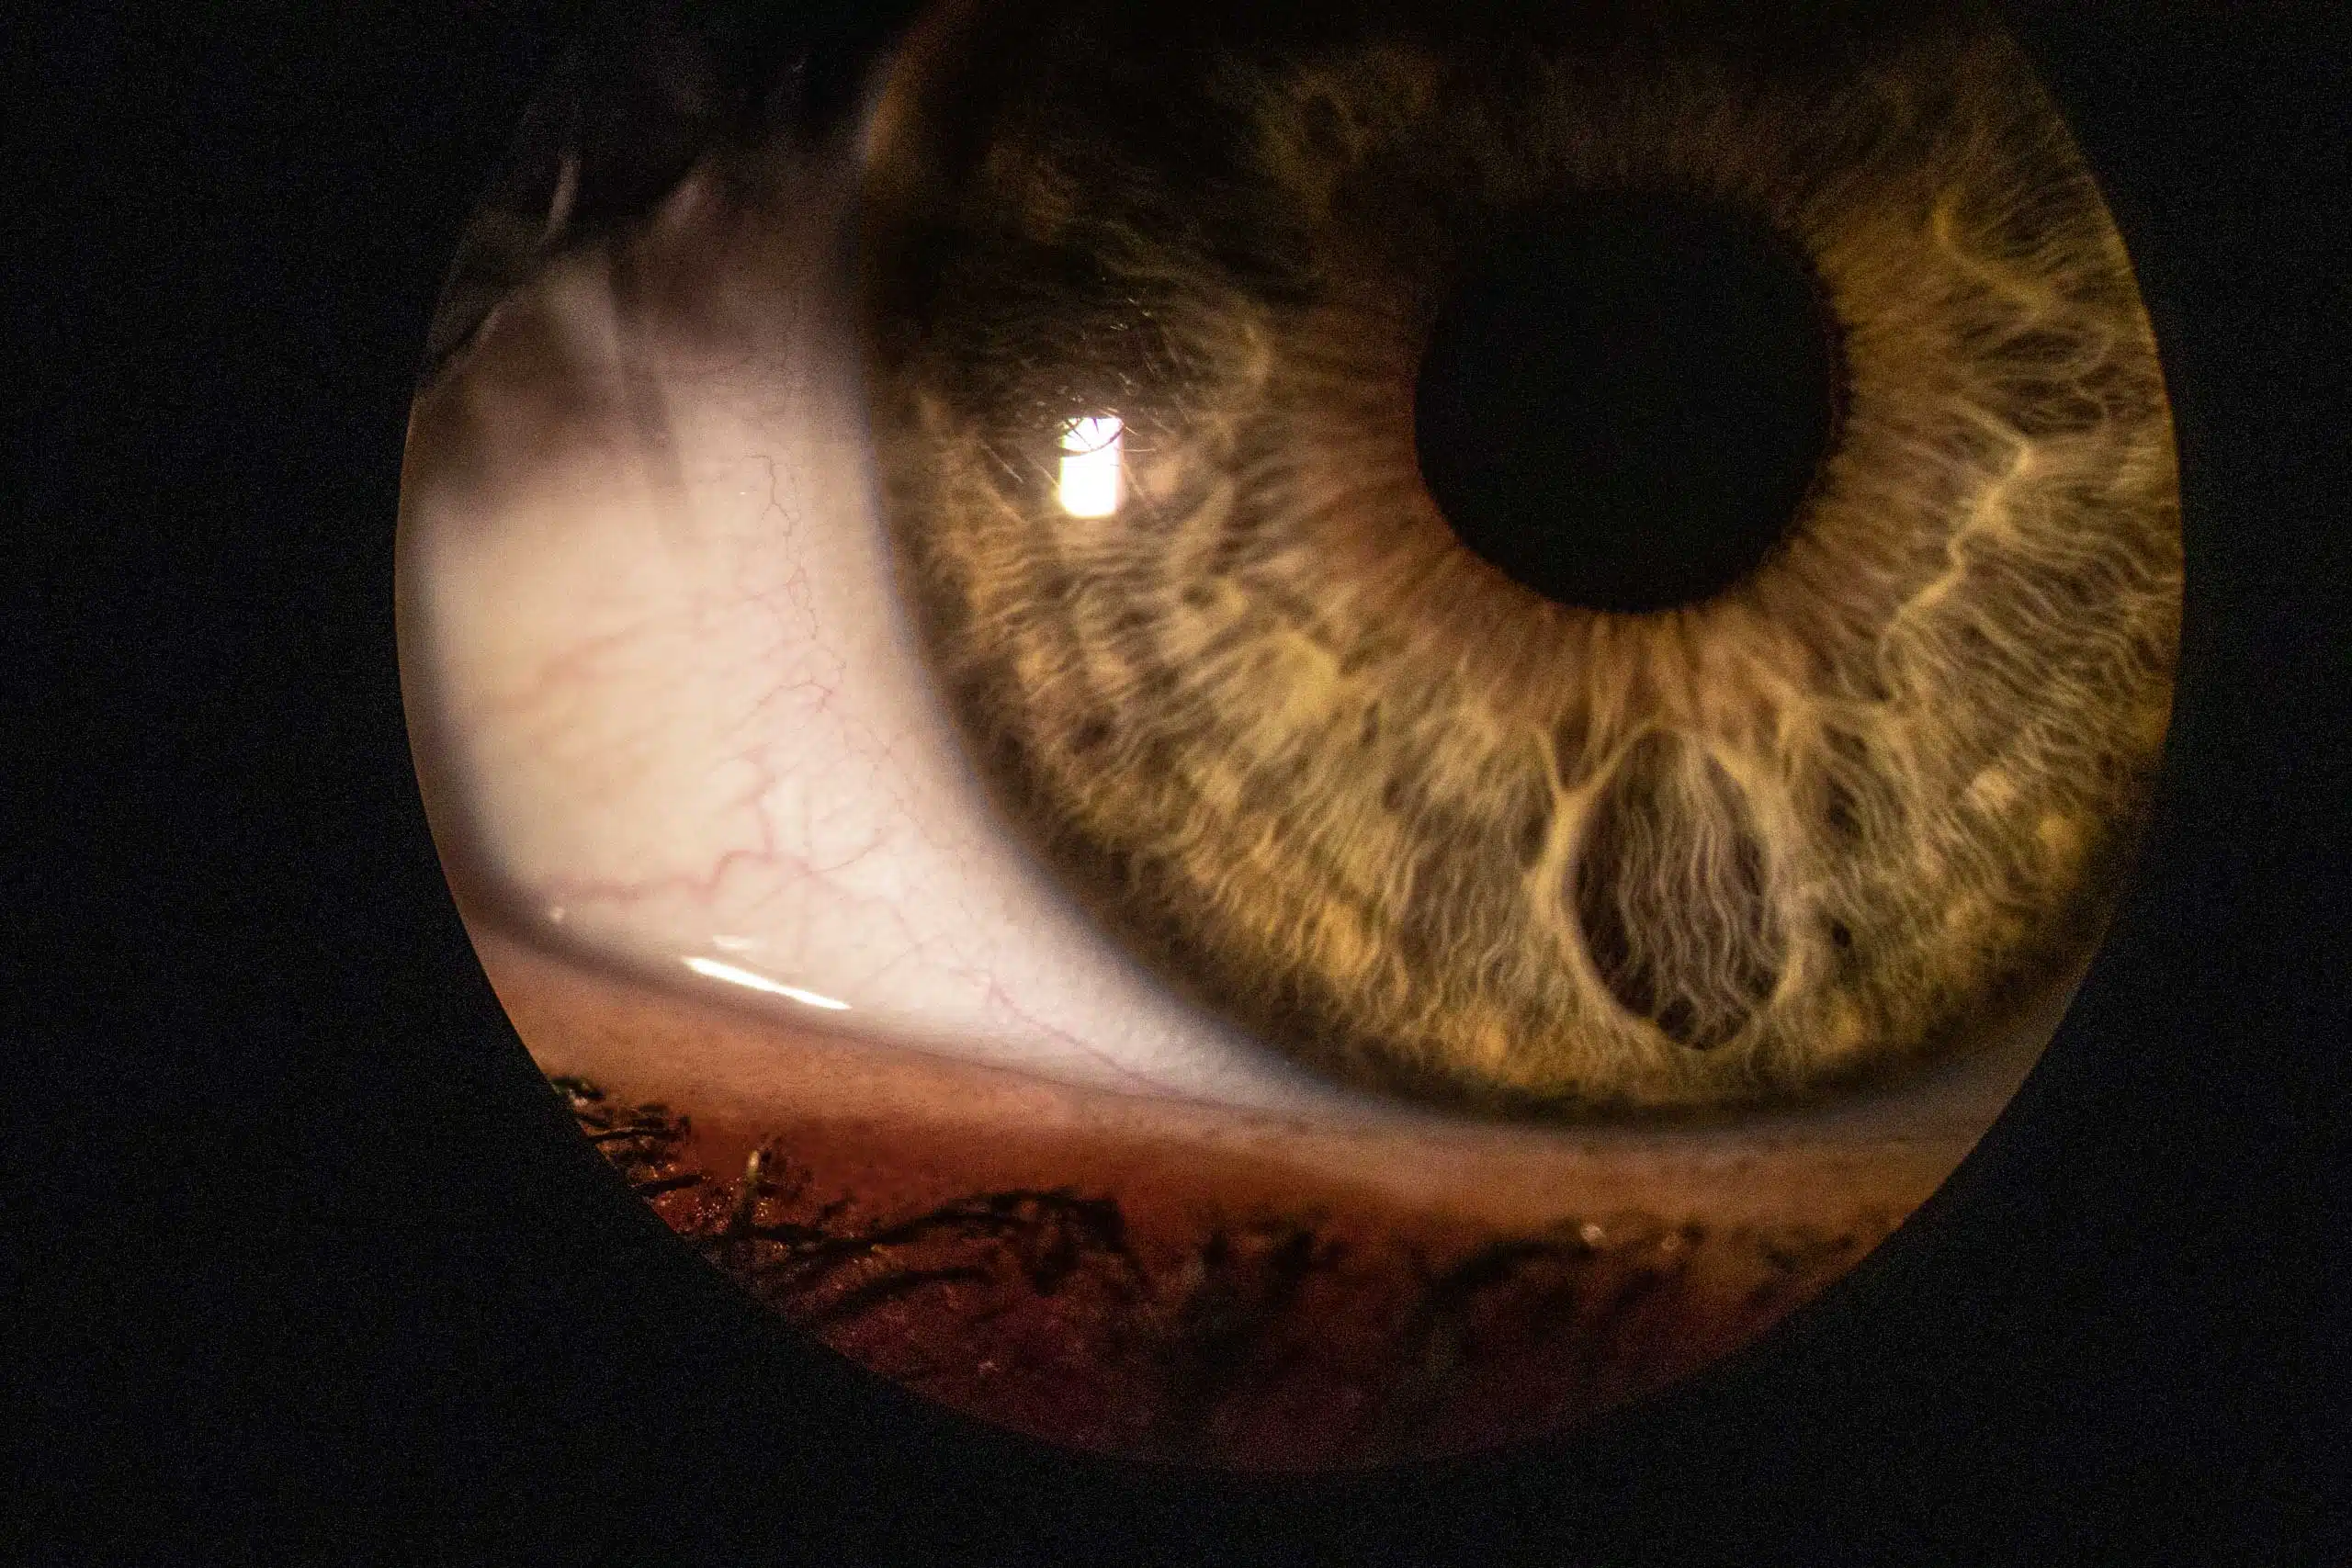

L’analisi visiva è un esame delle abilità che agiscono sulla visione. Valuteremo eventuali vizi refrattari, la visione binoculare e stereoscopica e come tutto ciò interagisce con la postura e con gli altri sensi.

La scelta della lente a contatto è un aspetto del nostro lavoro al quale dedichiamo una particolare attenzione. L’applicazione della lente a contatto prevede controlli precisi e rigorosi e un’adeguata informazione sulla loro gestione.

Le varie tipologie di lenti a contatto vanno dalle lenti morbide, per astigmatici, semirigide gas permeabili, per cheratocono e multifocali per coloro che vogliono vedere bene da vicino e da lontano.